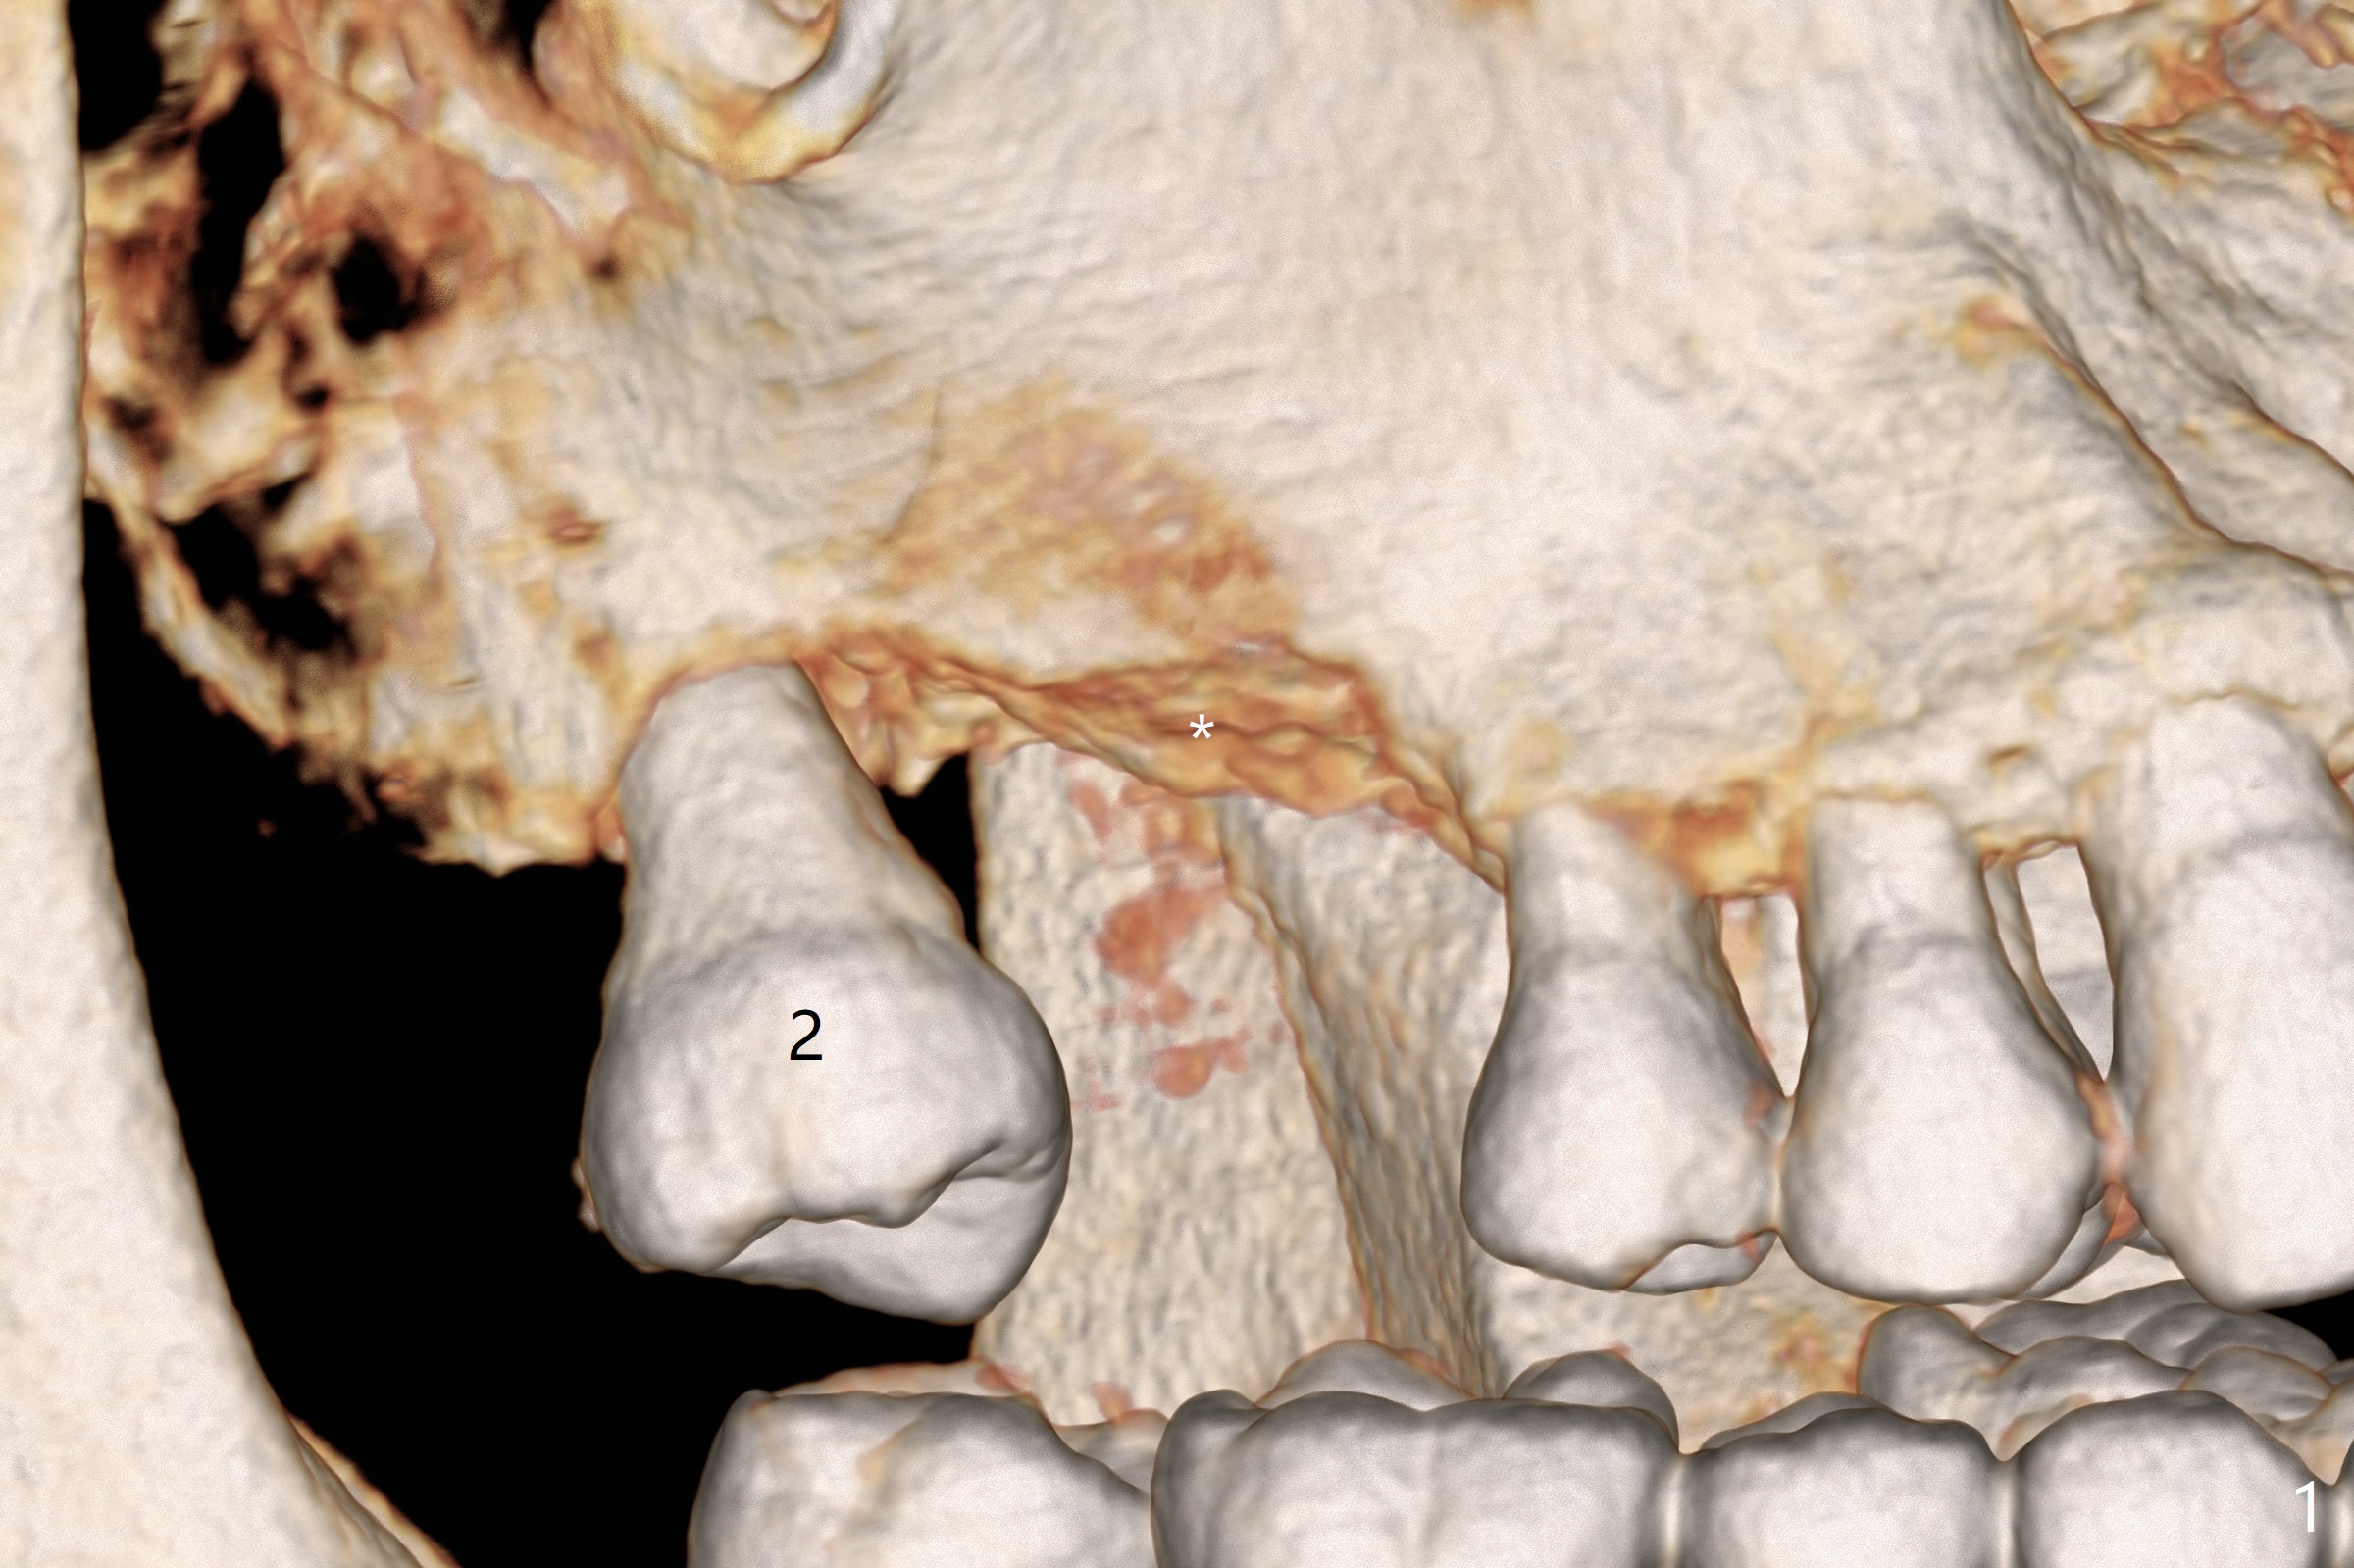

A 42-year-old man is interested in restoring the missing teeth #3 and 9 with implants after that at #14. It appears that the bone density at the ridge of #3 is low (Fig.1 *). Sinus lift may be accomplished directly with Magic Sinus Lifter. If not, use short Magic Drill with 1 and then 2 mm stoppers (Fig.2,3). Since the sinus floor is thicker mesially (Fig.2), establish osteotomy as mesial as possible. Lean Lindamann bur or Magic Drill mesially if needed. Place PRF and Vanilla Graft before insertion of a 4x9 mm dummy implant.